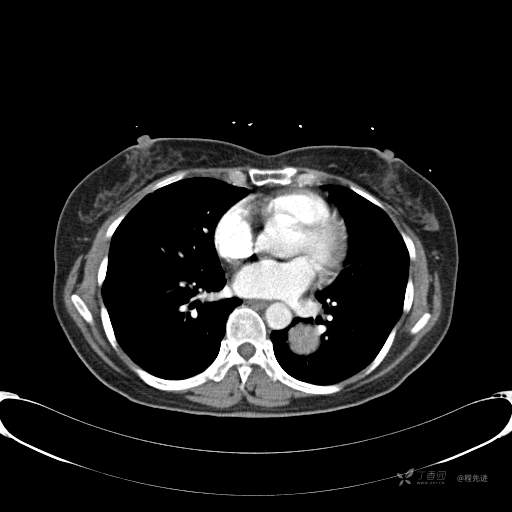

患者性别:女

患者年龄:57岁

简要病史:体检发现

CT增强

平扫CT值约40HU(未上传图像),增强后动脉期CT值约70HU,静脉期CT值约97HU。

肺硬化性血管瘤 (20)